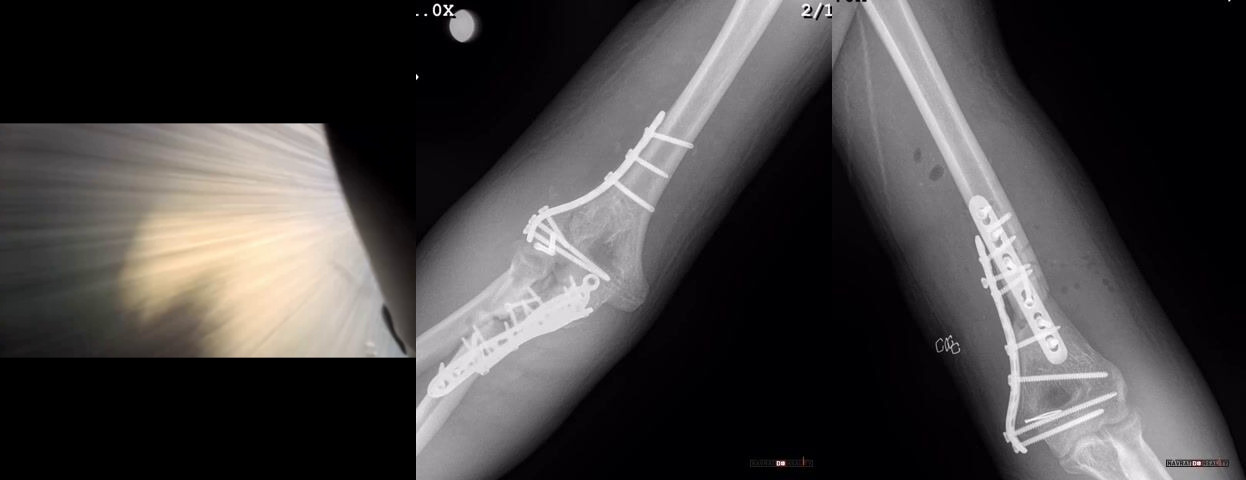

Motorkář nezvládl zatáčku a skončil s většími zraněními a mnoha šrouby v těle...

Drsná je silnice, šrouby a matice...

Screw it! Blahoželám